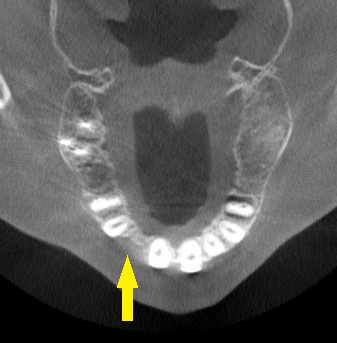

CTを撮影してみると、確かに骨が薄く、通常のインプラント埋入は無理だと判断しました。

下の写真が、手術前後のCTです。